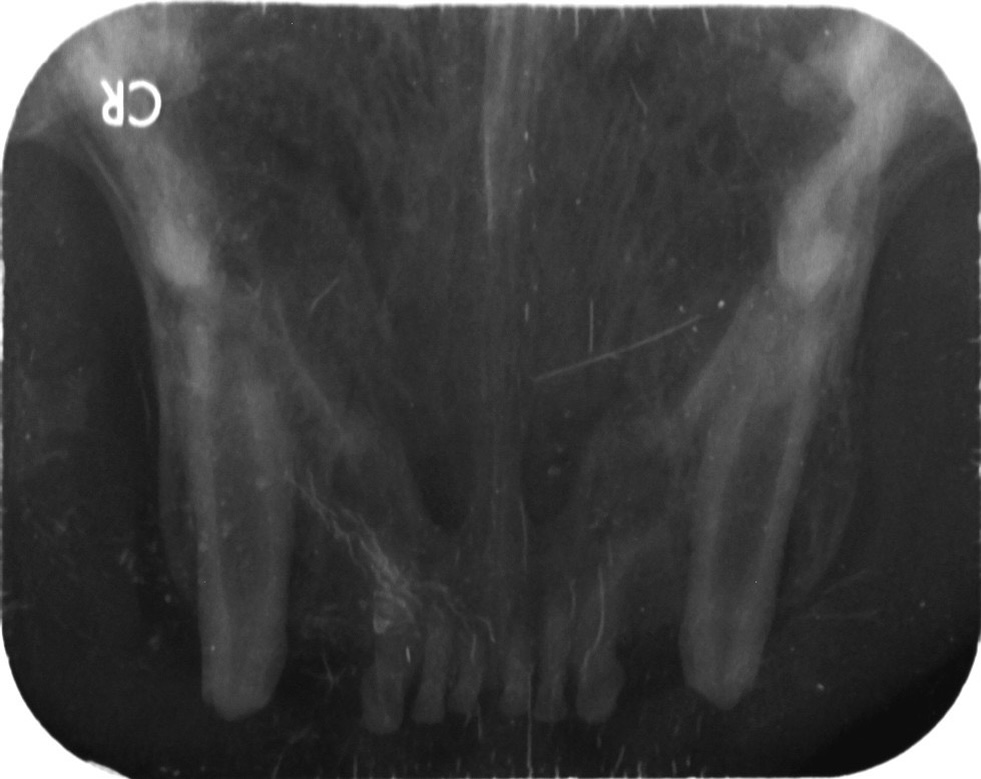

全口X光

全口齒科X光已經是口腔/齒科檢查的必備項目!

事實上,美國動物醫院協會(AAHA)等國際組織,已經將齒科X光列為口腔/齒科檢查的必備項目,只是目前在台灣,齒科X光的設備及觀念仍未普及。

研究發現,洗牙的同時若有輔助使用齒科X光能夠找出27.8%外觀正常的牙齒下潛藏的問題。本院也經常遇到只做洗牙而未拍攝齒科X光的寵物在洗牙後一個月內,就發生齒根膿瘍的狀況,顯示若只有洗牙把牙齒清潔乾淨而未透過X光偵測及處理牙根及牙周問題,往往沒多久還是會復發牙周問題,極有可能需再次麻醉治療。

築心特別引進POYE根尖X光照射系統以及齒科CR成像系統,能夠完整評估齒根狀況,減少傳統洗片的麻醉時間,能更完善地幫助受口腔問題所苦的寵物們!

術前拍全口X光